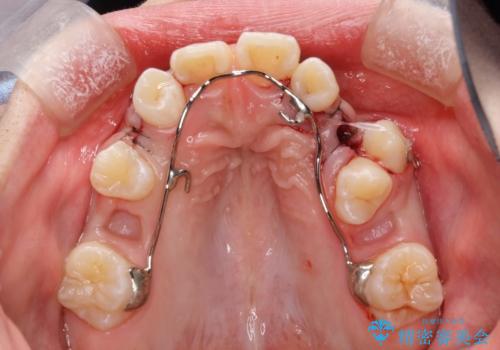

- 審美装置、リンガルアーチ

過剰歯と乳歯を抜歯後、リンガルアーチを用いて大まかな移動を行った後、マルチブラケットへ移行し、可及的に正常咬合へと誘導することを試みた。

乳歯・過剰歯を除去し、リンガルアーチを用いて埋伏していた犬歯を牽引、その他おおまかな動きを行った後、マルチブラケットにて永久歯の咬合を誘導しました。

一度装置を外し、セトリング含め咬合が安定したら、改めてマウスピース矯正などで微調整を行うとよいかもしれません。